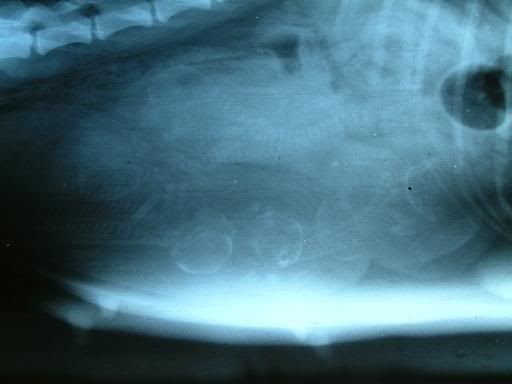

Rontgenfoto drachtige hond

Heeft iemand toevallig een rontgenopname van een drachtige hond? Een foto waar enkele pups (skeletjes) duidelijk op te zien zijn.

En waarvan ik de foto ook mag gebruiken voor een werk voor school

wat mooi te zien al die skeletjes, is dit een foto van jouw hond?